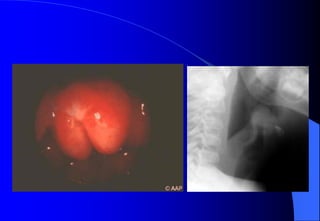

+ X quang phoåi.

+ X quang thanh quaûn thaúng, nghieâng (ôû

caû hai thì hít vaøo vaø thôû ra) = Daáu hieäu

Steeple .

Dấu hiệu Steeple